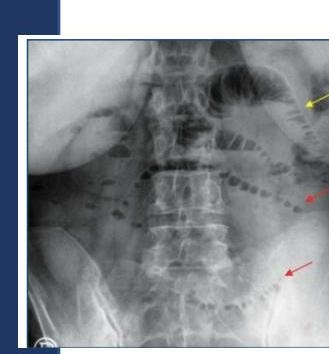

# OCLUSIÓN INTESTINAL ## DEFINICIÓN Se define como la **INTERRUPCIÓN DEL TRÁNSITO INTESTINAL**, lo que impide expulsar gases y heces por el recto. El bloqueo de la luz intestinal se da en su mayoría por factores extrínsecos (adherencias, hernia inguinal, hernia de pared estrangulada) y en pocas ocasiones por obstrucción de la luz. **ADHERENCIAS PERITONEALES**: son bandas fibrosas entre órganos o tejidos o ambos en la cavidad abdominal que normalmente están separados. TIPOS DE ÍLEO | PARALÍTICO / ADINÁMICO | Existe una causa funcional que altera el peristaltismo. La causa más frecuente es la cirugía abdominal (íleo reflejo postquirúrgico). Tras la cirugía, el intestino delgado es el primero en recuperar la movilidad a las 24 horas, seguido del estómago 48 horas, el colon tarda 3 -5 días. | | :--: | :-- | | OBSTRUCTIVO / MECÁNICO | Existe una causa orgánica que lo produce como son las barreras físicas que obstruyen la luz. | | ESPÁSTICO | Hiperactividad descoordinada del intestino que se observa en la intoxicación por metales pesados, porfiria y uremia. Se debe tratar la enfermedad sistémica. | | ÍLEO DE LA OCLUSIÓN VASCULAR | Movilidad descoordinada del intestino isquémico | ## EPIDEMIOLOGÍA - LAS **ADHERENCIAS SON LA CAUSA MÁS COMÚN DE OCLUSIÓN INTESTINAL** - Responsables en 65 - 75 % de los casos (mortalidad de 3.5 - 6%) - El 70% de las adherencias responde a manejo conservador, un 30% requiere manejo quirúrgico. - En el intestino delgado, la obstrucción mecánica es el trastorno quirúrgico más frecuente. ## FACTORES DE RIESGO - Adherencias - **Hernia inguinal** (primera causa en pacientes sin cirugía previa) - **Hernia de pared estrangulada** - Neoplasias - Íleo por cálculo biliar - **Enfermedad de Crohn** - **Vólvulo** - **Intususcepción** - Divertículo de Meckel - **Cuerpo Extraño** # CLÍNICA - **DOLOR ABDOMINAL TIPO CÓLICO** + **NÁUSEA**, **VÓMITO** Y **ESTREÑIMIENTO** - El vómito es más prominente en las obstrucciones proximales - La distensión se asocia al íleon distal. - Los ruidos intestinales son hiperactivos al principio, luego son mínimos | INTESTINO DELGADO | Dolor abdominal, vómitos (fecaloides si es distal), distensión abdominal, hiperperistaltismo con ruidos metálicos | | :--: | :--: | | INTESTINO GRUESO | Dolor y distensión abdominal Vómitos y estreñimiento Incapacidad de expulsar gases y heces | **Obstrucción Estrangulada**: Dolor abdominal desproporcionado, taquicardia, fiebre, leucocitosis y acidosis. ## DIAGNÓSTICO **GOLD STANDARD: RADIOGRAFÍA DE ABDOMEN** (En decúbito y de pie) + Tele de Tórax de pie. ## TRIADA DE RX: - Asas en Intestino delgado dilatadas (+3 cm de diámetro) - Niveles hidroaéreos - Escasez de aire en el colon  Radiografía en decúbito con dilatación de asas de intestino delgado con válvulas conniventes (separado de la base y por el extremo en contacto)  Signo de Collar de Perlas: representa pequeñas cantidades de aire atrapado en las válvulas del intestino delgado, predominantemente lleno de líquido. Se presenta en obstrucción mecánica de ID. DATOS EN **TAC**: 1. Dilatación proximal del intestino 2. Descompresión distal del intestino 3. Contraste luminal que no pasa más allá de la zona de transición 4. Colon con poco gas o líquido 5. Signo de las heces (burbujas)   Signo de **PILAS DE MONEDAS**: Pliegues intestinales engrosados, lisos, rectos y perpendiculares al eje longitudinal de la luz. # TRATAMIENTO ## CONSERVADOR ## SONDA NASOGÁSTRICA / TUBO INTESTINAL LARGO - El 90% de las obstrucciones de ID se resuelven con **SNG y REPOSICIÓN HIDROELECTROLÍTICA** - Debe mantenerse durante 48 - 72 horas. - Si existe obstrucción por estrangulación, obstrucción maligna, hernias encarceladas, cuerpo extraño, enteritis por radiación, peritonitis o abdomen agudo, debe considerarse **cirugía**. ## QUIRÚRGICO Deberá considerarse el manejo invasivo en los siguientes casos: A. **Íleo mecánico intestinal por más de 3 días** B. Drenaje por SNG al tercer día >500 ml C. Edad menor a 40 años o adherencias complejas D. **Obstrucción completa** del intestino delgado (sin aire en intestino grueso) y CPK mayor a 130 Considerar **Cirugía INMEDIATA** en los siguientes casos: - Cirugía dentro de las 6 semanas previas al cuadro de oclusión - Cuadro no resuelto con manejo conservador en las 48-72 horas a pesar de utilizar medio de contraste hidrosoluble por SNG - Presencia de líquido intraperitoneal, edema del mesenterio y signo de las heces en intestino delgado - Dolor abdominal mayor a 4, resistencia abdominal, leucocitos 10,000 o más, PCR 75 mg - Datos de **estrangulación**: fiebre, taquicardia, leucocitosis, acidosis metabólica. ## LAPAROTOMÍA EXPLORADORA 1. La incisión debe permitir tener una adecuada exposición y visibilidad 2. Identificar sitio y causa de obstrucción, si no es obvio, hay que descomprimir el intestino hasta encontrarla 3. Si el intestino está isquémico hay riesgo de ruptura con salida de contenido a cavidad abdominal 4. Después de corregir obstrucción se deben explorar los cuatro cuadrantes. 5. Si es requerido, realizar resección intestinal y anastomosis primaria. ## LAPAROSCOPÍA Solo se realizará en un grupo selecto de pacientes como abordaje - Casos de un primer episodio de oclusión intestinal por **adherencias** - Diámetro intestinal menor a 4 cm . - Sospecha de una banda - Antecedente de 2 o menos laparotomías - Antecedente de apendicectomía o colecistectomía puede someterse a laparoscopía. # ANEXOS